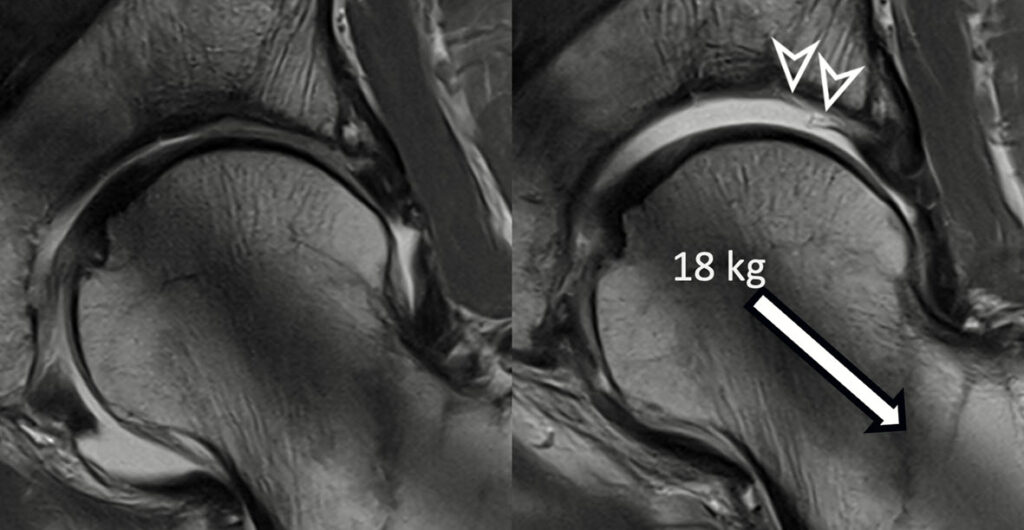

→ Alle Gelenke des Bewegungsapparates – Prothesenbildgebung

→ Artho-MRT aller Gelenke, Hüfte mit Traktion